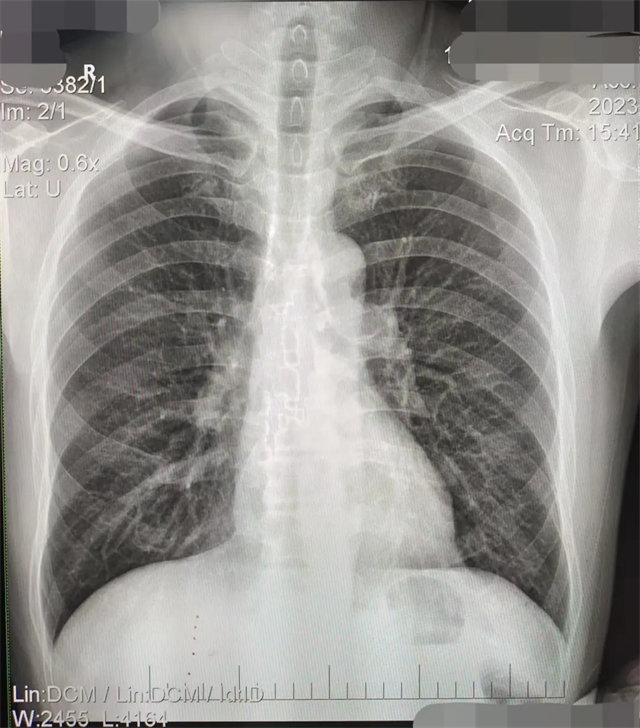

缺陷:雙側(cè)胸鎖關(guān)節(jié)不對稱,且有手機顯影。

解決:去除手機后,使患者左側(cè)緊貼成像件曝光。